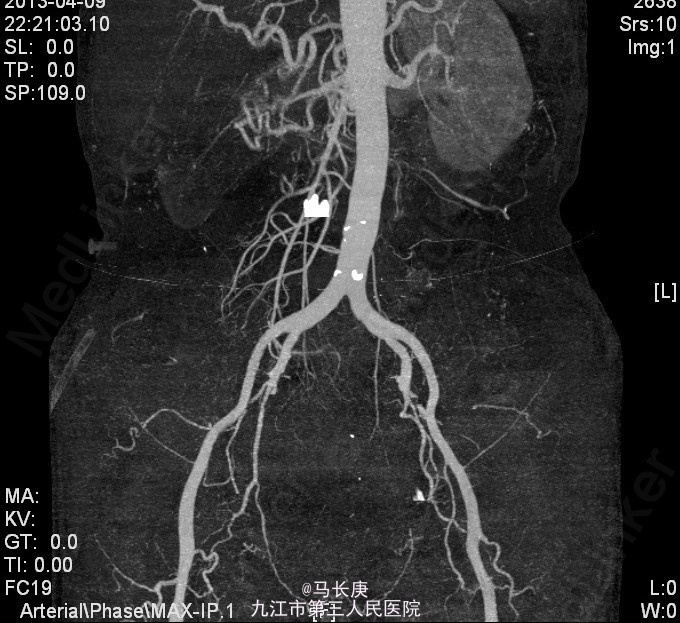

3、查体:无明显异常 4、辅助检查:当地人民医院泌尿系CT平扫+增强:1.右侧输尿管结石2.右肾占位?(未见报告),我科fish(+)CTU:肾盂癌,侵蚀右肾包膜,左肾囊肿,慢性胆囊炎。双肾核素扫描:右肾GFR:9.5,左肾48.5

5、考虑右肾盂癌 6、入院后给予双肾核素扫描、CTU检查,考虑右肾盂癌,给予抗炎、补液、治疗。现病情平稳。 术前诊断:右肾盂癌、胆囊炎、左肾囊肿、右侧输尿管结石、贫血、低蛋白血症、胆囊炎,后行右肾癌根治术,手术顺利,术后恢复较好,术后病理示:肾恶性肿瘤(高分化肉瘤)。